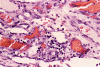

Panel A, B and F are taken from the dermal-epidermal junction. Panel B, C, D, and E are taken from the same area. Panel F, G, H, and I are taken from the same area

The tumor appears to be centered on the dermis and does not involve breast parenchyma in the sections examined A (not shown). On low-magnification (Panel A, B and F), the lesional tissue is a highly cellular and vascular tumor in the dermis. The large areas of hemorrhage ("blood-lake") and dilated vascular channels (Panel A, and F) probably correspond to the "red nodules and yellow patches" on physical examination. Although the tumor extends deeply into the subcutaneous tissue (not shown here), there is no evidence of invasion in to the epidermal layer (Panel A, B and F). The histology of this tumor varies in different areas. In some areas, it appears as a densely packed spindle cell tumor with exuberant and irregular and anastomosing vascular channels (Panel B, C, and D). The endothelial cells protrudes into the vascular channels and had enlarged, hyperchromatic nuclei with  prominent nucleli. In another area, the lesion contains numerous ectactic and anastomosing vascular channels (Panel F, G, H, and I). Pleomorphic changes are also prominent in the vascular cells in these areas. On immunohistochemistry, the tumor cells are immunoreactive for CD31, CD34 (not shown).